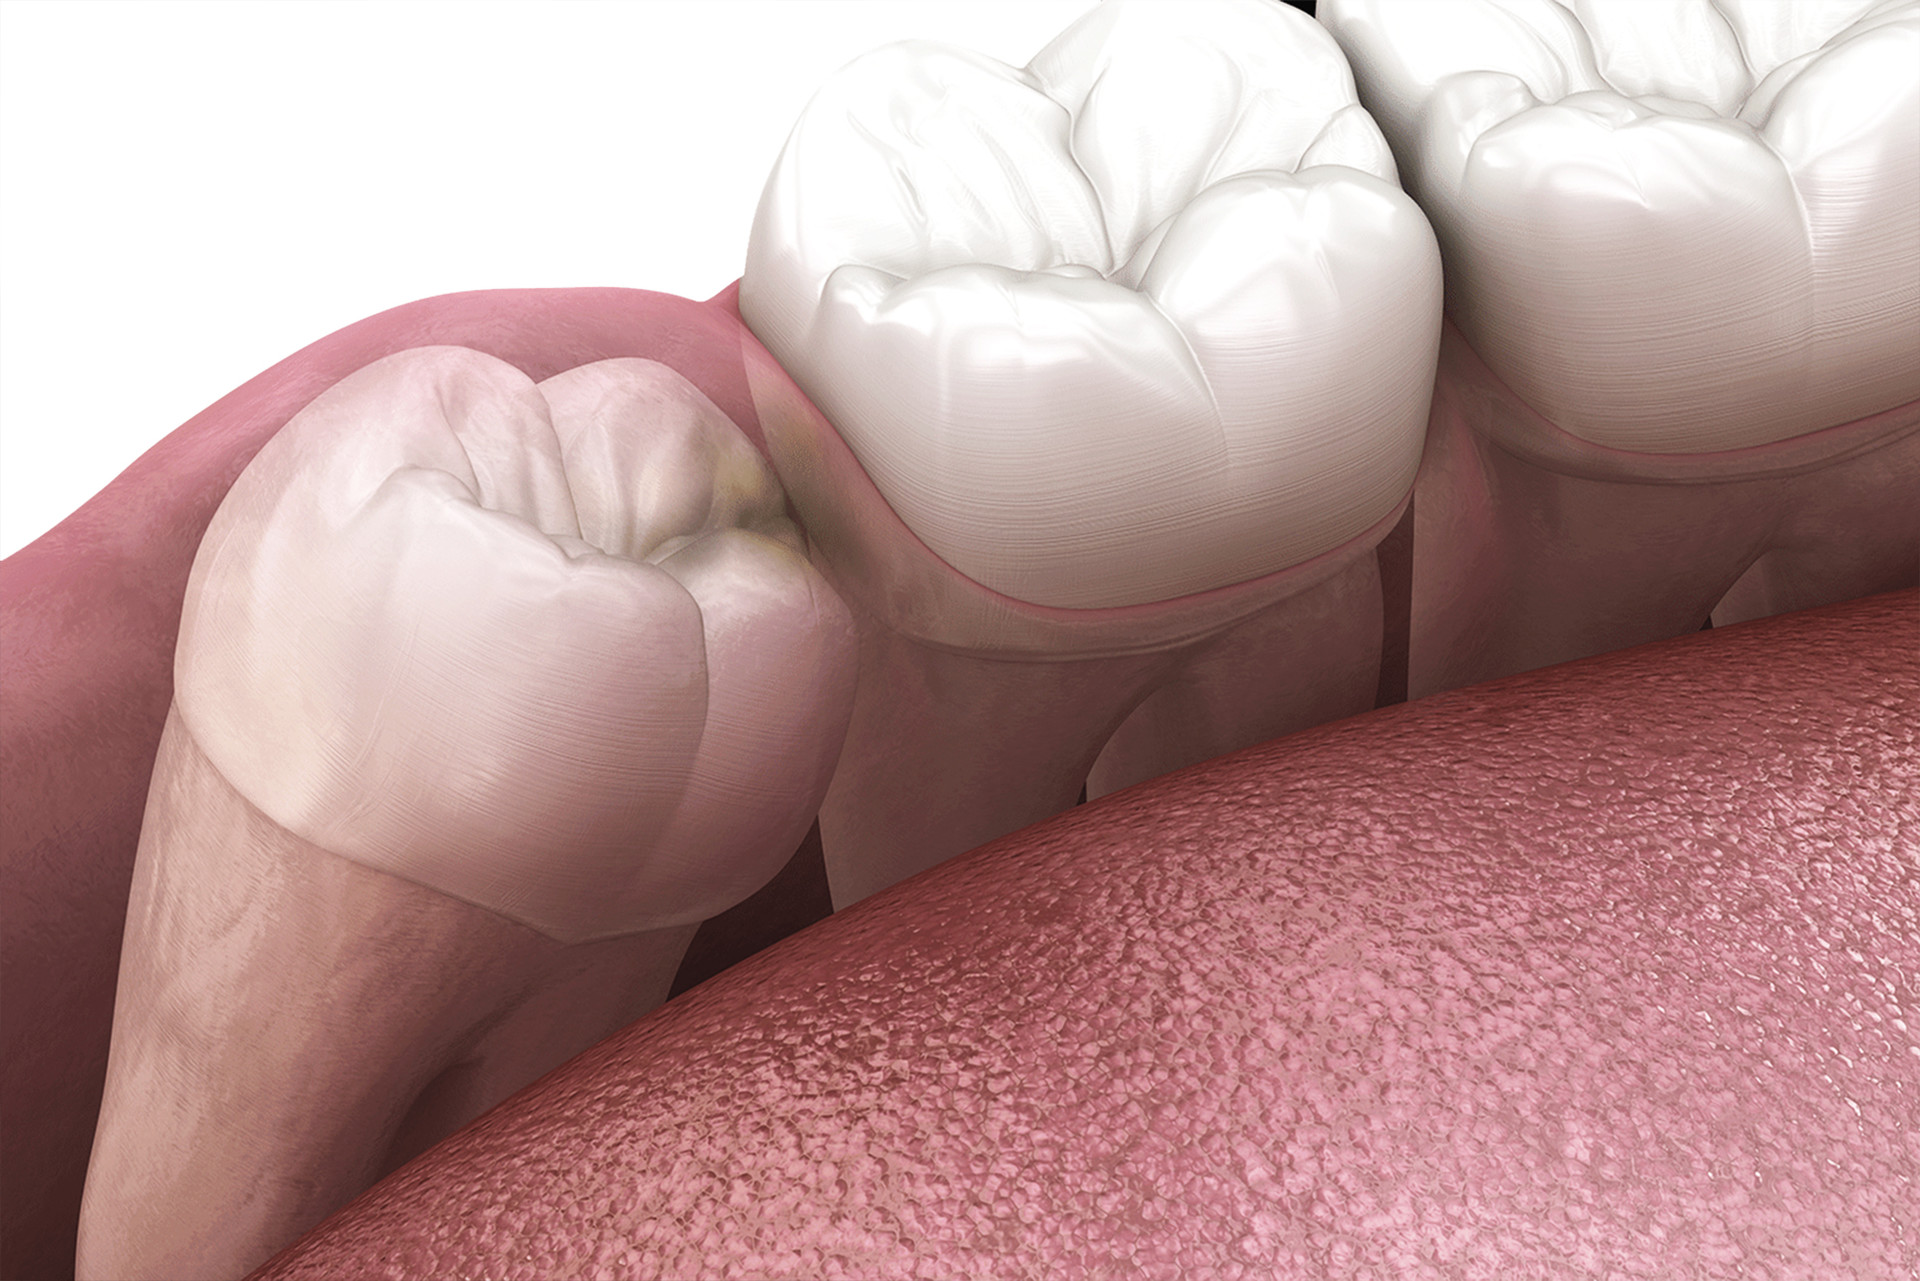

정상적으로 자라는 사랑니도 있지만, 대부분의 경우

턱 뼈 공간의 부족으로 옆으로 누워나거나 매복하는 등

좋지 못한 경우가 많으며 아래 사랑니는 뿌리가 아래턱 신경을

손상시킬 가능성이 있고, 위 사랑니의 경우 상악동 천공 등의

문제를 일으킬 위험이 크기 때문에 발치를 권장드리고 있습니다.